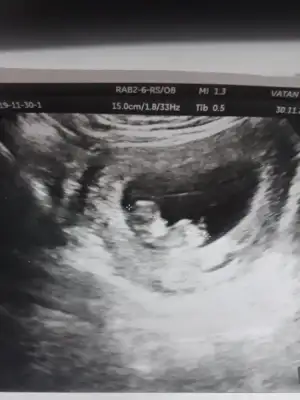

Biri 9+5 digeri 11+5 doktor bacaklati kapali dedi resimde de sirti donuk sanki yanlis miyim☺

• 20191216_185754.webp

20191216_185754.webp

23,5 KB · Görüntüleme: 53